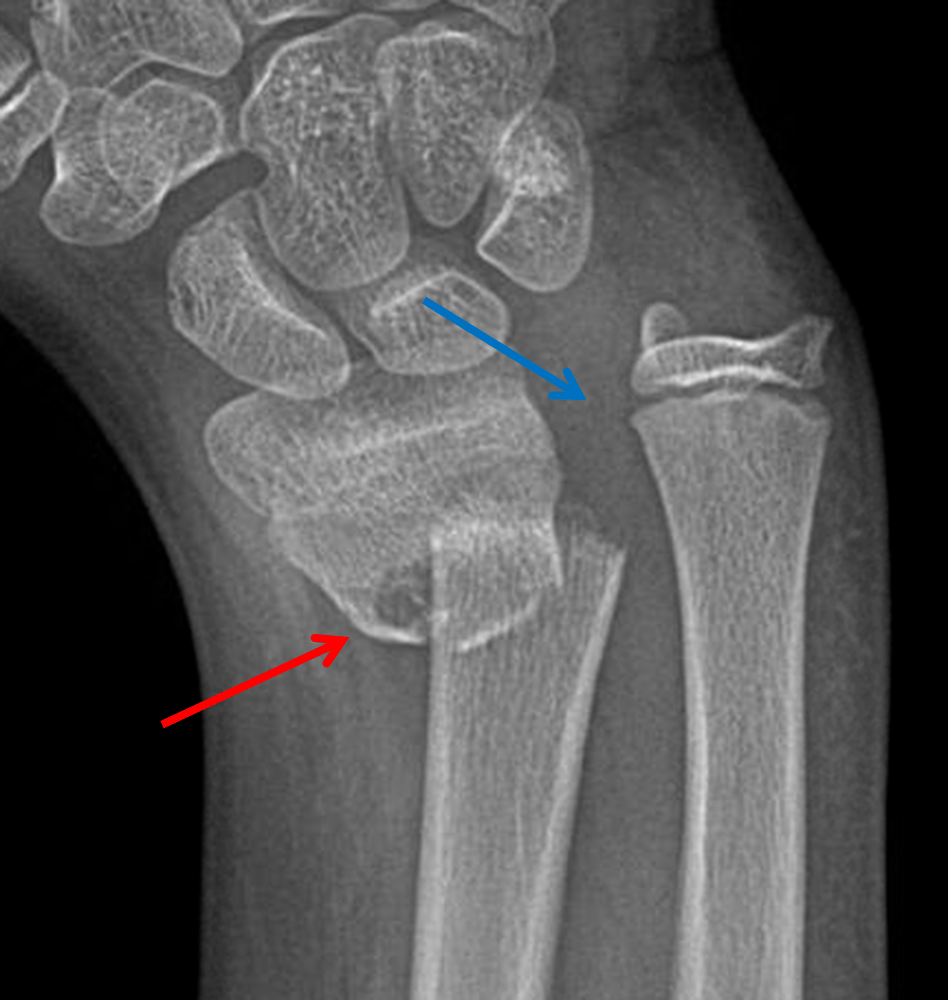

The pain started 72 days back when the patient sustained a road traffic accident and fell from his motorbike on an outstretched hand, since then, he noticed the deformity in his forearm, and he first thought it was a simple contusion or bruise. Galeazzi fracture-dislocations are usually managed acutely due to the apparent deformity, pain, and disability suffered by the patient, we have searched the literature and only found one case reporting a chronic Galeazzi fracture-dislocation, and therefore, we present our experience with this rare injury.Ī 27-year-old man of Eastern Asian descent presented to our outpatient clinic with a complaint of the right forearm pain and deformity for over 2 months. In pediatrics, however, Galeazzi fracture can be amenable to closed treatment with satisfactory outcomes due to several reasons including thick periosteum, stronger ligamentous restraints, and higher bone modeling capacity. Historically Galeazzi fractures is adult were treated with open reduction and internal fixation of the radius fracture with or without DRUJ repair and pinning, the is largely due to the highly unsatisfactory outcomes following closed treatment and chronic disability. On the other hand, two classification systems classify the fracture based on its distance from the DRUJ, the most commonly used is the one by Retting, in which the fracture is either more than 7.5 cm away from the DRUJ or less, the main rationale behind this classification is that fractures < 7.5 cm are more prone to DRUJ instability according to the results of this study. Several classification systems have been proposed for Galeazzi fracture-dislocation, the first was described by Walsh, in which the fracture was classified based on its angulation, the position of the forearm (supination of pronation) on axial loading of the fractures will contribute to its apex (apex volar or apex palmar). The IOM also has a complex structure of bands and cords that prevent translation of the radius and ulna and also transmit axial and rotational forces, the central band is the main restraint and stabilizer within the IOM. Galeazzi fractures are inherently unstable due to the disruption of the DRUJ and possible disruption of the interosseous membrane (IOM), the triangular fibrocartilage complex (TFCC) is the main stabilizer of the DRUJ and the dorsal and volar radioulnar ligaments are the most important ligaments within the TFCC.

Galeazzi fracture represents a distinct spectrum of forearm injuries that represent approximately 7% of adult and 3% of pediatric forearm fractures, they are a unique injury which involves a fracture of the radial diaphysis, along with disruption or dislocation of the distal radioulnar joint (DRUJ).